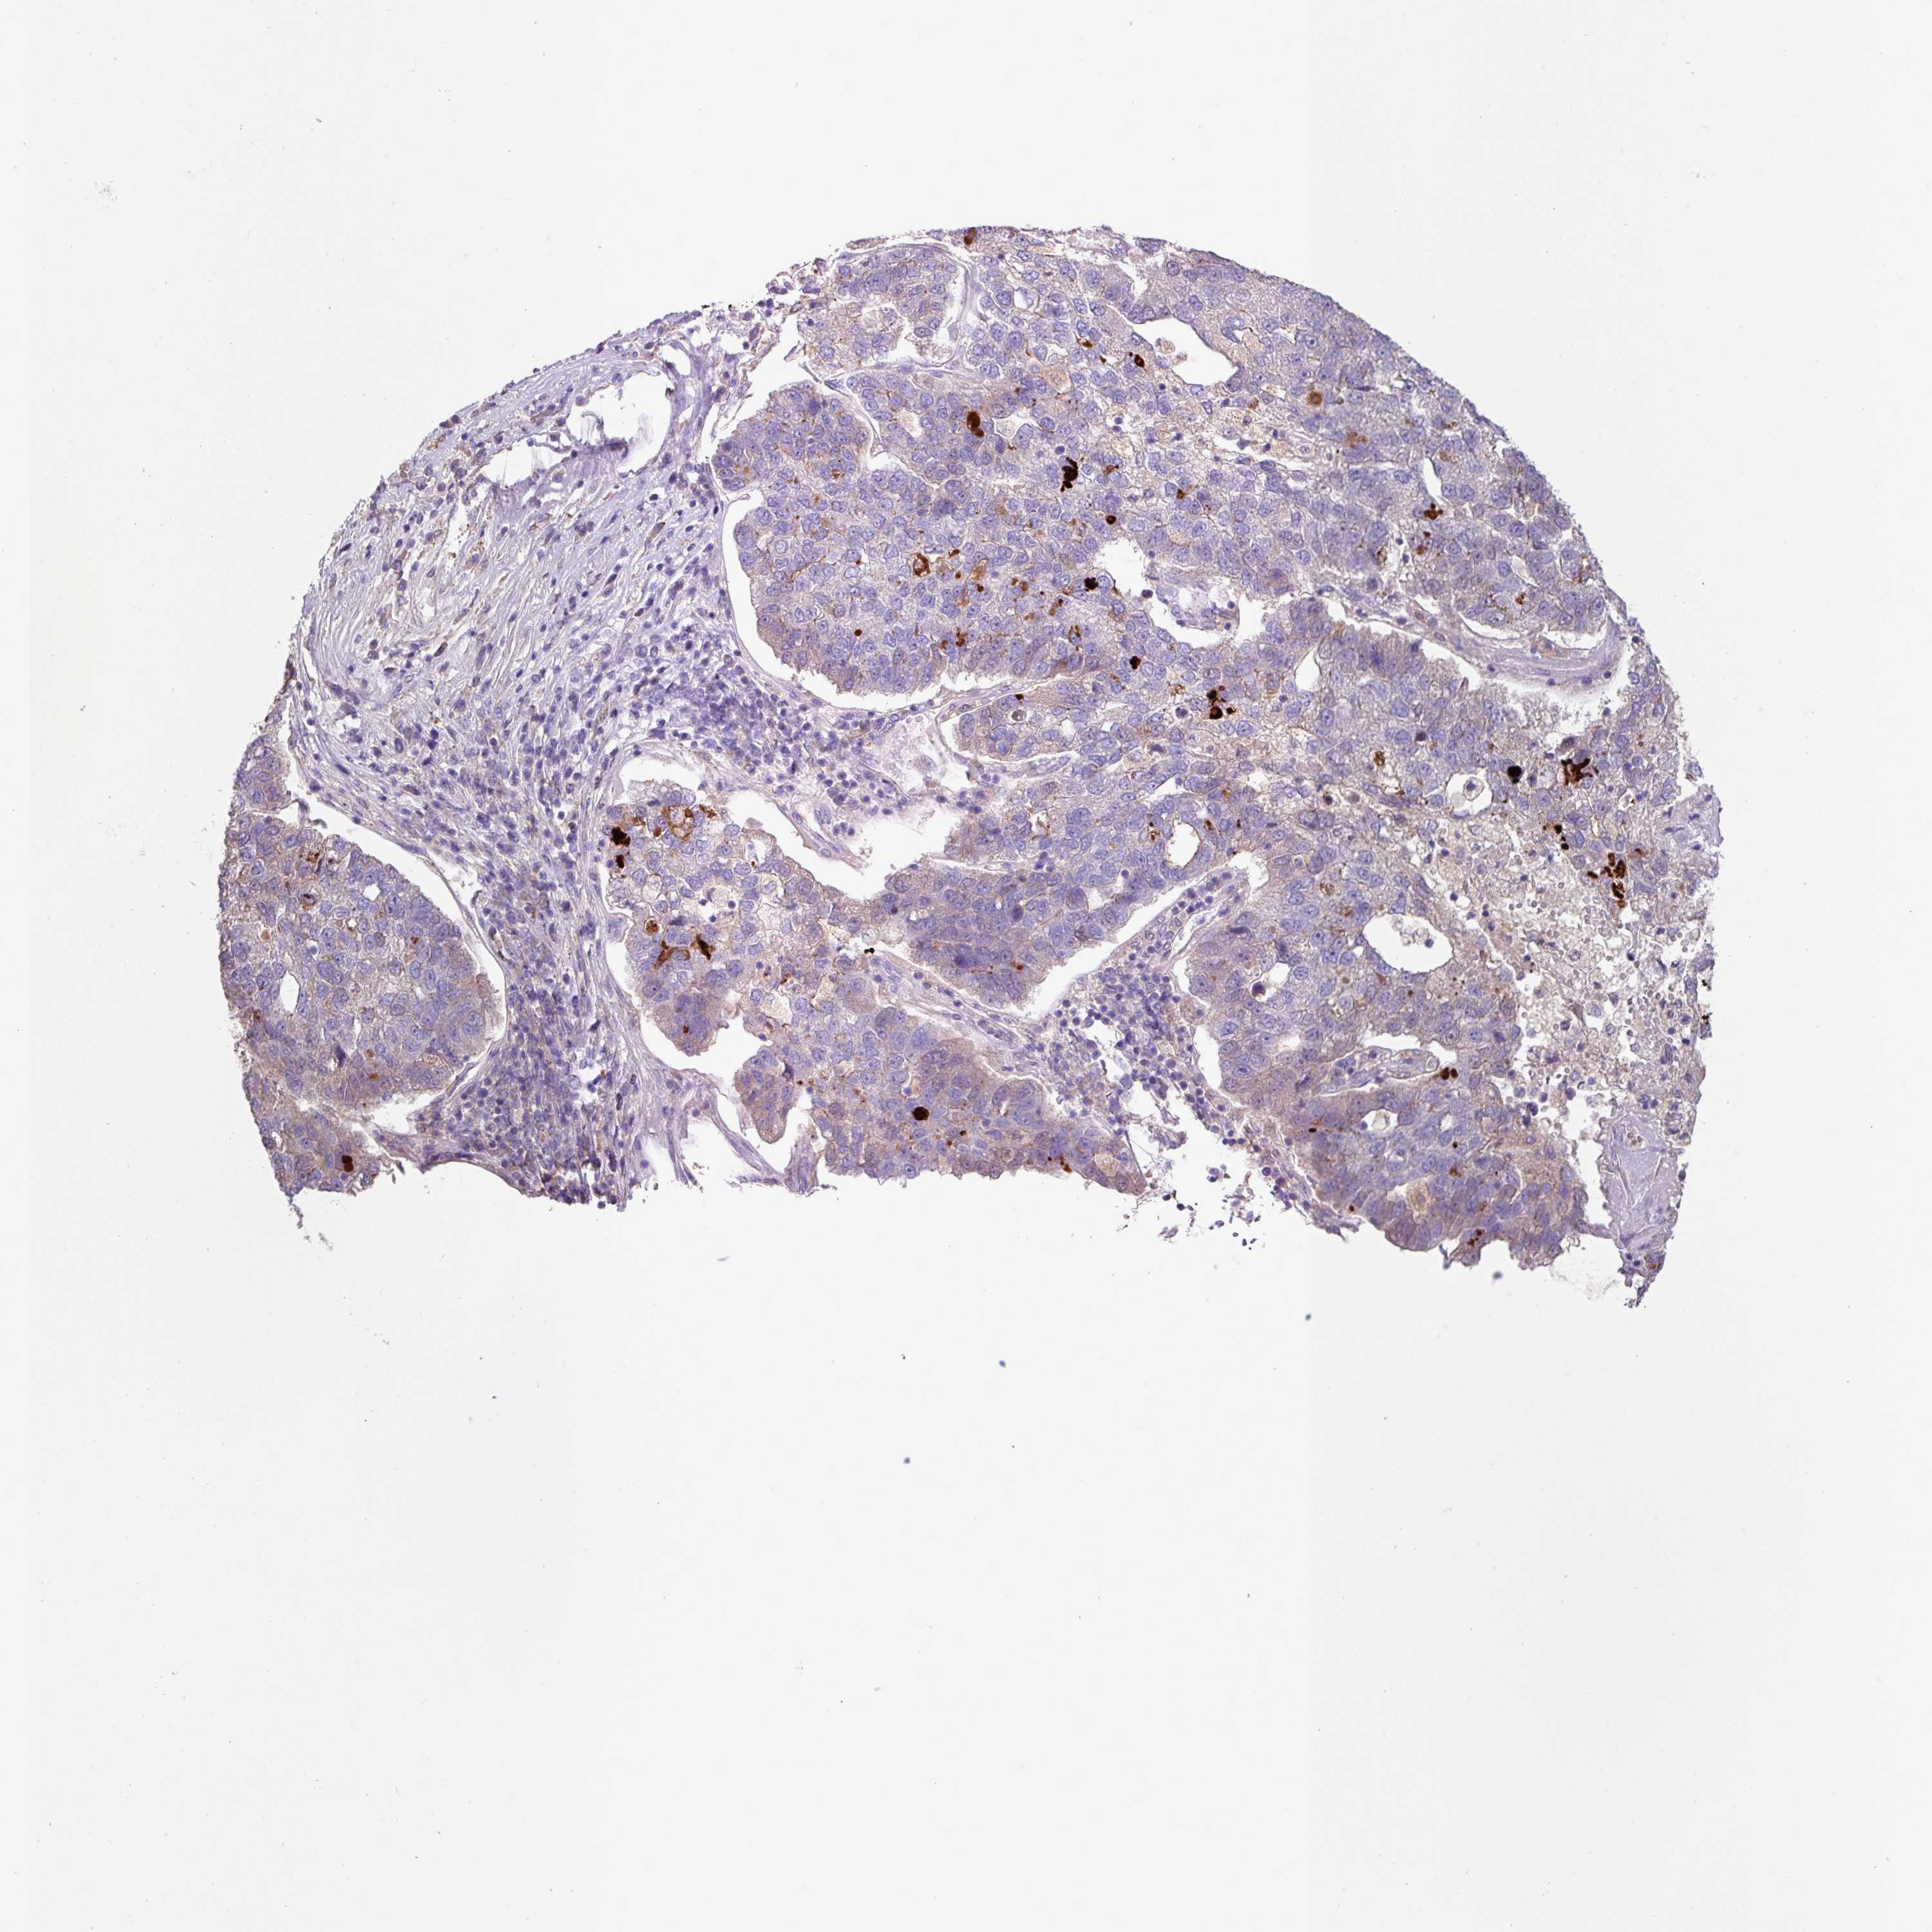

PANCREATIC CANCER - Protein expressioni

A mouse-over function shows sample information and annotation data. Click on an image to view it in a full screen mode. Samples can be filtered based on level of antibody staining by selecting one or several of the following categories: high, medium, low and not detected. The assay and annotation is described here.

Note that samples used for immunohistochemistry by the Human Protein Atlas do not correspond to samples in the TCGA dataset.

Antibody stainingi

Antibody staining in the annotated cell types in the current human tissue is reported as not detected, low, medium, or high, based on conventional immunohistochemistry profiling in selected tissues. This score is based on the combination of the staining intensity and fraction of stained cells.

Each image is clickable and will lead to virtual microscopy that enables deeper exploration of all samples and also displays staining intensity scores, fraction scores and subcellular localization as well as patient and tissue information for each sample.

Antibody HPA052835

Staining

High

Medium

Low

Not detected

Intensity

Strong

Moderate

Weak

Negative

Quantity

>75%

75%-25%

<25%

None

Location

Nuclear

Cytoplasmic/membranous

Cytoplasmic/membranous,nuclear

Adenocarcinoma, NOS